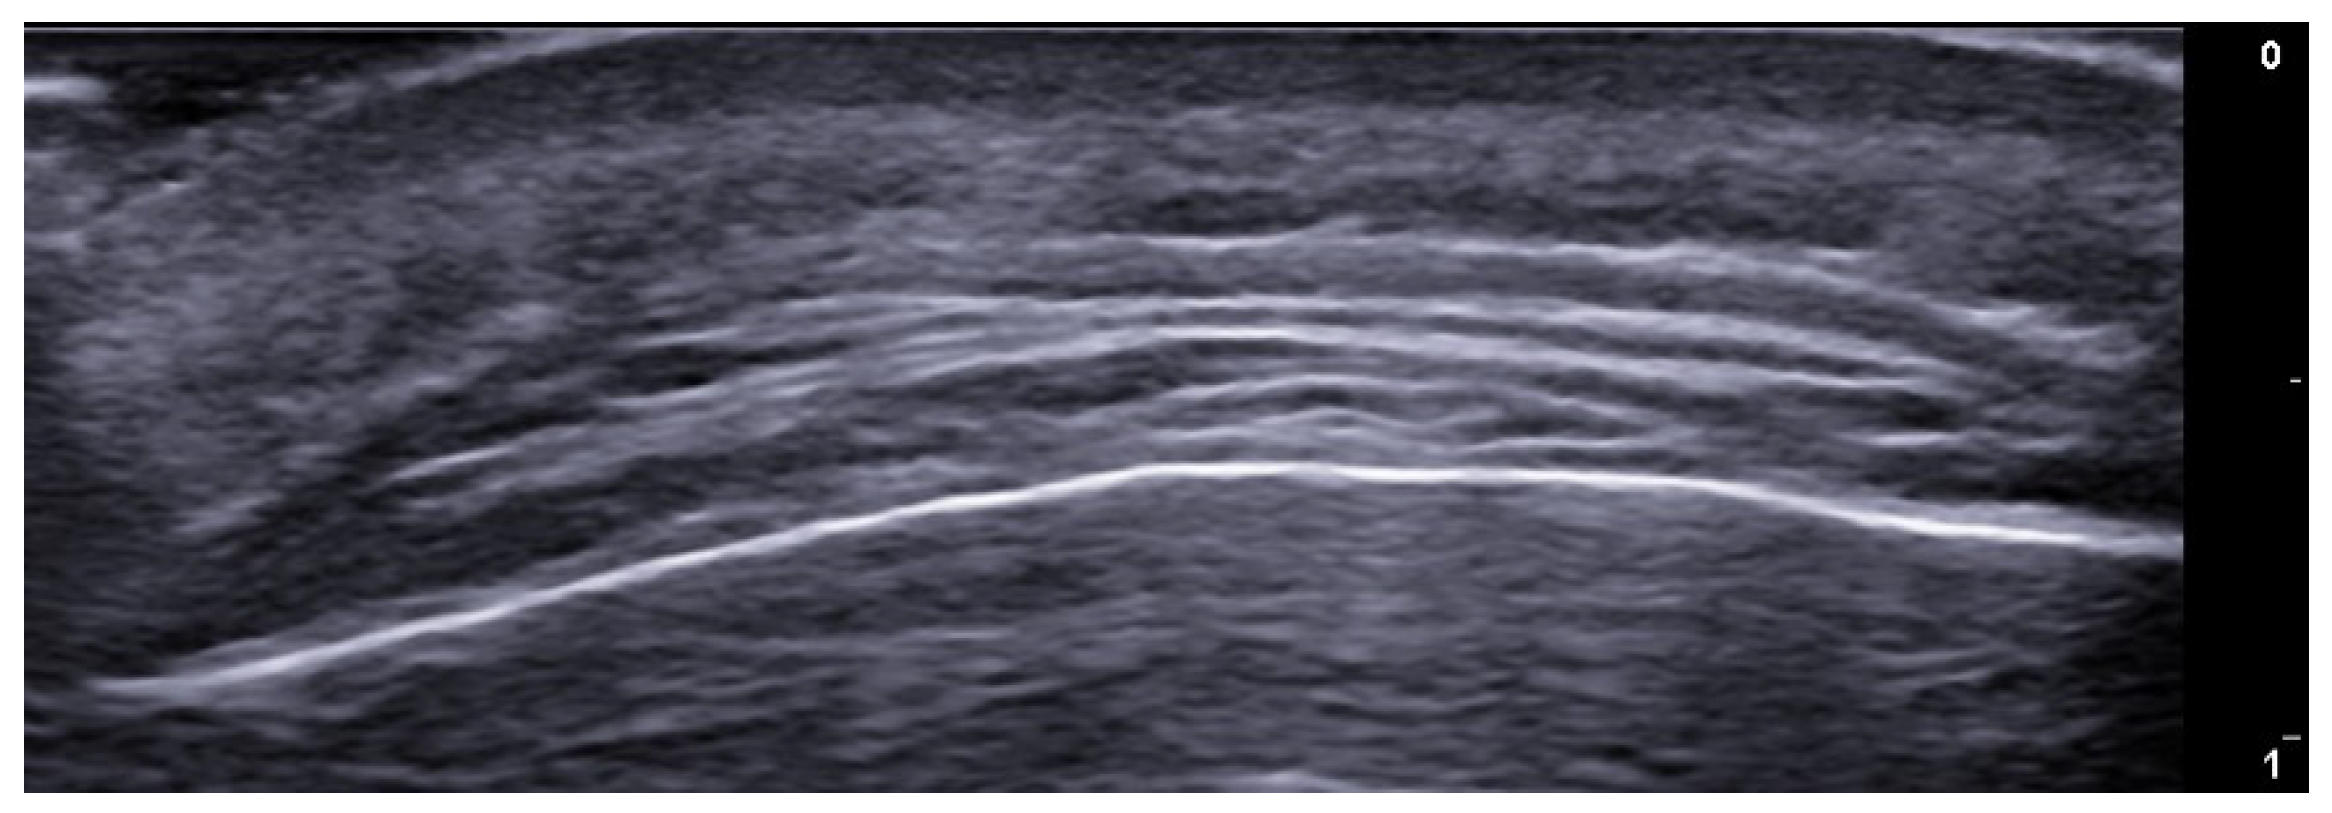

- Berritto, D.; Iacobellis, F.; Rossi, C.; Reginelli, A.; Cappabianca, S.; Grassi, R. Ultra high-frequency ultrasound: New capabilities for nail anatomy exploration. J. Dermatol. 2017, 44, 43–46. [Google Scholar] [CrossRef]

- Szymoniak-Lipska, M.; Polańska, A.; Jenerowicz, D.; Lipski, A.; Żaba, R.; Adamski, Z.; Dańczak-Pazdrowska, A. High-Frequency Ultrasonography and Evaporimetry in Non-invasive Evaluation of the Nail Unit. Front. Med. 2021, 8, 686470. [Google Scholar] [CrossRef]

- Sechi, A.; Wortsman, X.; Tosti, A.; Iorizzo, M. Advances in image-based diagnosis of nail disorders. J. Eur. Acad. Dermatol. Venereol. 2024; online ahead of print. [Google Scholar] [CrossRef]